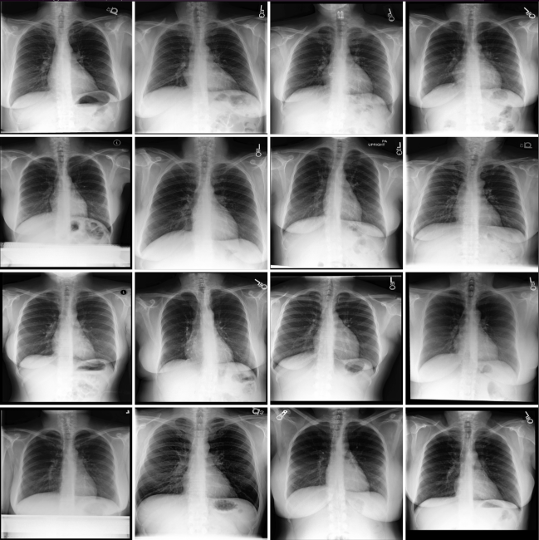

Refer to caption

Figure 2: SAE-Rad identifies clinically relevant and interpretable features within radiological images. We illustrate a number of pathological and instrumentation features relevant for producing radiology reports. We add annotations (green arrows) to emphasize the presence of each feature.

Figure 2 illustrates randomly selected monosemantic visual features from SAE-Rad. As can be seen, the SAE learns human-interpretable visual concepts despite the homogeneity and relatively small size of the dataset. These include dextroscoliosis of the spine (Fig. 2; feature 1), bilateral opacifications (Fig. 2; feature 2), unilateral pleural effusions (Fig. 2; feature 3), and the presence of instrumentation – in this case a pacemaker (Fig. 2; feature 4). In Fig. 3, we illustrate an example ‘findings’ section for a CXR with a number of pathological findings; SAE-Rad is capable of detecting multiple relevant pathologies for a given image. Like other radiology report generation systems, SAE-Rad can miss findings. However, it can also occasionally describe a relevant finding which is otherwise missing from the reference report – an example relating to the presence of a dialysis catheter is shown in Fig. 3.